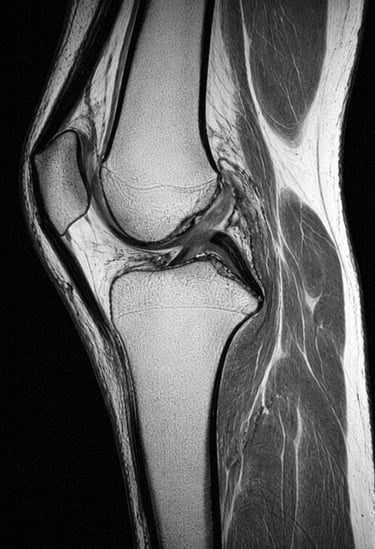

L’IRM du genou est un examen d’imagerie médicale qui permet d’analyser en détail les structures internes du genou.

L’IRM (Imagerie par Résonance Magnétique) est un examen qui utilise un champ magnétique pour obtenir des images précises du genou.

Elle permet de visualiser :

les ménisques

les ligaments

le cartilage

les tendons

l’os

Contrairement à la radiographie, elle permet d’explorer les tissus mous.

Que montre une IRM du genou

L’IRM permet de détecter :

lésions du ménisque

rupture des ligaments

arthrose du genou

inflammation articulaire

épanchement de synovie

C’est un examen très précis pour le diagnostic.